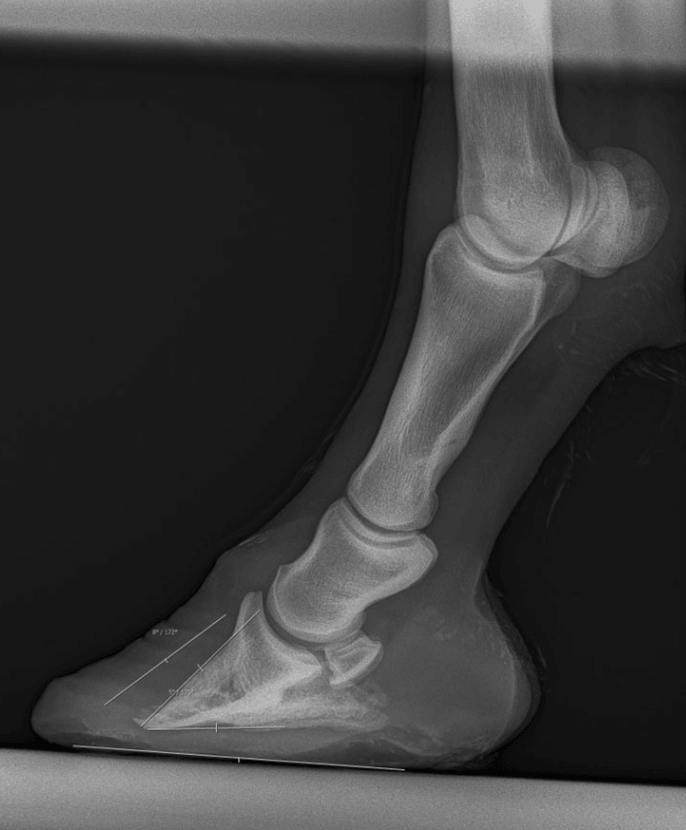

- Eine Röntgenaufnahme: Unverzichtbares Hilfsmittel zur Identifizierung der WLD

Eine Röntgenaufnahme stellt in bestimmten Fällen ein interessantes Hilfsmittel bei der Erkennung und Diagnose der Erkrankung der weißen Linie im Pferdehuf dar, da sie detaillierte Informationen über die inneren Strukturen liefern kann.

Darstellung von Knochenstrukturen :

Röntgenaufnahmen ermöglichen eine genaue Darstellung der knöchernen Strukturen des Hufes, einschließlich der Wand, der Sohle und des Strahls. Betroffene Bereiche können auf dem Röntgenbild als verschwommene oder verblasste Bereiche erscheinen.

Erkennung abnormaler Bereiche :

Indem sich die WLD in den Huf gräbt, entstehen Bereiche und Hohlräume, die visuell schwer zu erkennen sind. Mithilfe von Röntgenaufnahmen können diese abnormalen Bereiche entdeckt werden, die auf das Vorhandensein einer Erkrankung der weißen Linie hinweisen könnten, selbst in einem frühen Stadium, in dem äußere Anzeichen noch fehlen.

Die Beurteilung von Stützstrukturen :

Das Röntgenbild hilft bei der Beurteilung der Beschaffenheit der Stützstrukturen des Hufes, wie z. B. der Hornschicht und der Anatomie des Hufes.

Überwachung der Fortschritte :

Röntgenaufnahmen bieten auch eine effektive Möglichkeit, die Entwicklung der Krankheit der weißen Linie im Laufe der Zeit zu verfolgen. Dadurch können Pferdemediziner die Wirksamkeit der angewandten Behandlungen bewerten und die Interventionen entsprechend anpassen.